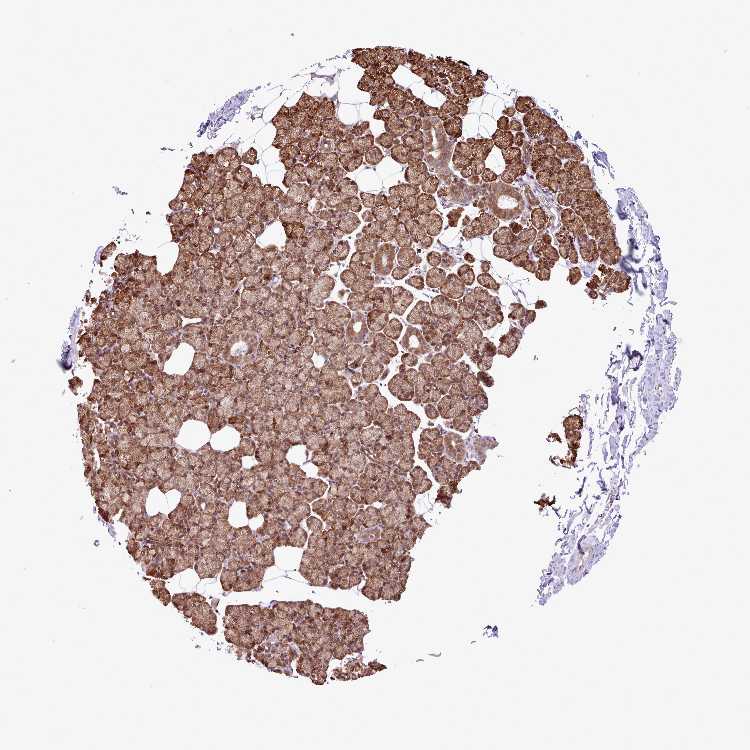

SOFT TISSUE 2 - Antibody stainingi

Antibody staining in the annotated cell types in the current human tissue is reported as not detected, low, medium, or high, based on conventional immunohistochemistry profiling in selected tissues. This score is based on the combination of the staining intensity and fraction of stained cells.

Each image is clickable and will lead to virtual microscopy that enables deeper exploration of all samples and also displays staining intensity scores, fraction scores and subcellular localization as well as patient and tissue information for each sample.

Antibody HPA051413

Chondrocytes Low

Fibroblasts Medium